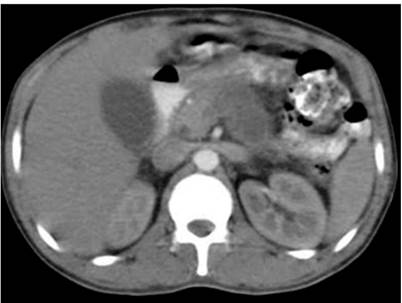

As a result, the patient was referred to a secondary care center, where he was diagnosed with hyperamylasemia (595 mg/dL) associated with hyperbilirubinemia (Table 1). Furthermore, positive acute phase reactants and imaging findings, using an enhanced computed tomography (CT) scan, were compatible with acute pancreatitis (Balthazar grade D) (Figure 1), which was classified as moderate to severe according to the clinical severity index, with an APACHE II (Acute Physiology and Chronic Health Evaluation II) score of 7. Consequently, management was initiated with fluid resuscitation, antibiotic treatment with ampicillin/sulbactam, and cessation of feeding.

Figure 1 Abdominal CT scan: hepatomegaly and fat infiltration, pancreatitis (Balthazar D) with severity index score of 5, bilateral pleural effusion, and small amount of free fluid in the abdominal cavity. Source: Own elaboration.